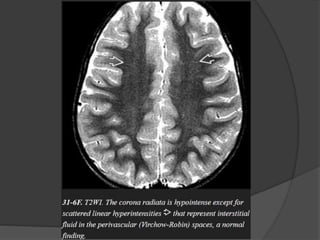

 Normal myelination… Hyperintense on T1 &

Hypointense on T2.

 T1W parallel increase in lipids while T2W

correlates to the period of maturation of myelin

sheath.

SUPRATENTORIAL

 Internal capsule

Posterior limb

Anterior limb

 Thalamus

 Pre / postcentral gyri

 Corpus callosum

Splenium

Genu

 Centrum semiovale

 Optic radiations

 Subcortical U fibers

T1WI T2WI

Birth Birth

3 mth 3 – 6 mth

1 mth 8 – 12 mth

3 – 4 mth 6 mth

6 mth 8 mth

Birth – 1 mth 3 mth

3 mth 3 mth

3 – 8 mth 8 – 18 mth